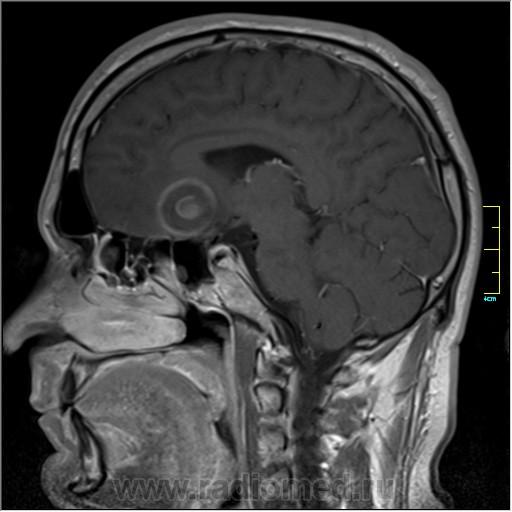

Пациентка направлена на исследование с диагнозом "Гипертонический криз", энцефалопатия неуточненная.

Sag T2:

частично функционирующая аневризма

Иначе говоря, аневризма с хронической геморрагией, т.к. мы видим фракции крови различного возраста.

По-моему, аневризма с пристеночными тромбами.

Постепенное пристеночное образование тромбов приводит к появлению типичного для аневризмы феномена -слоистости МР сигнала в полости аневризмы. Данная картина демонстрирует слоистый характер тромботических масс в полости аневризмы .Функционрирующая часть имеет низкий сигнал во всех режимах сканирования. Дополнительно-перифокальный отек.

А может более корректно интерпретировать как частично тромбированная аневризма... Уж коь речь идет о фракциях, ну то есть о тромбе по сути.... Ну и плюс перфокальный отек головного мозга (вероятнее цитотоксический+вазогенный).